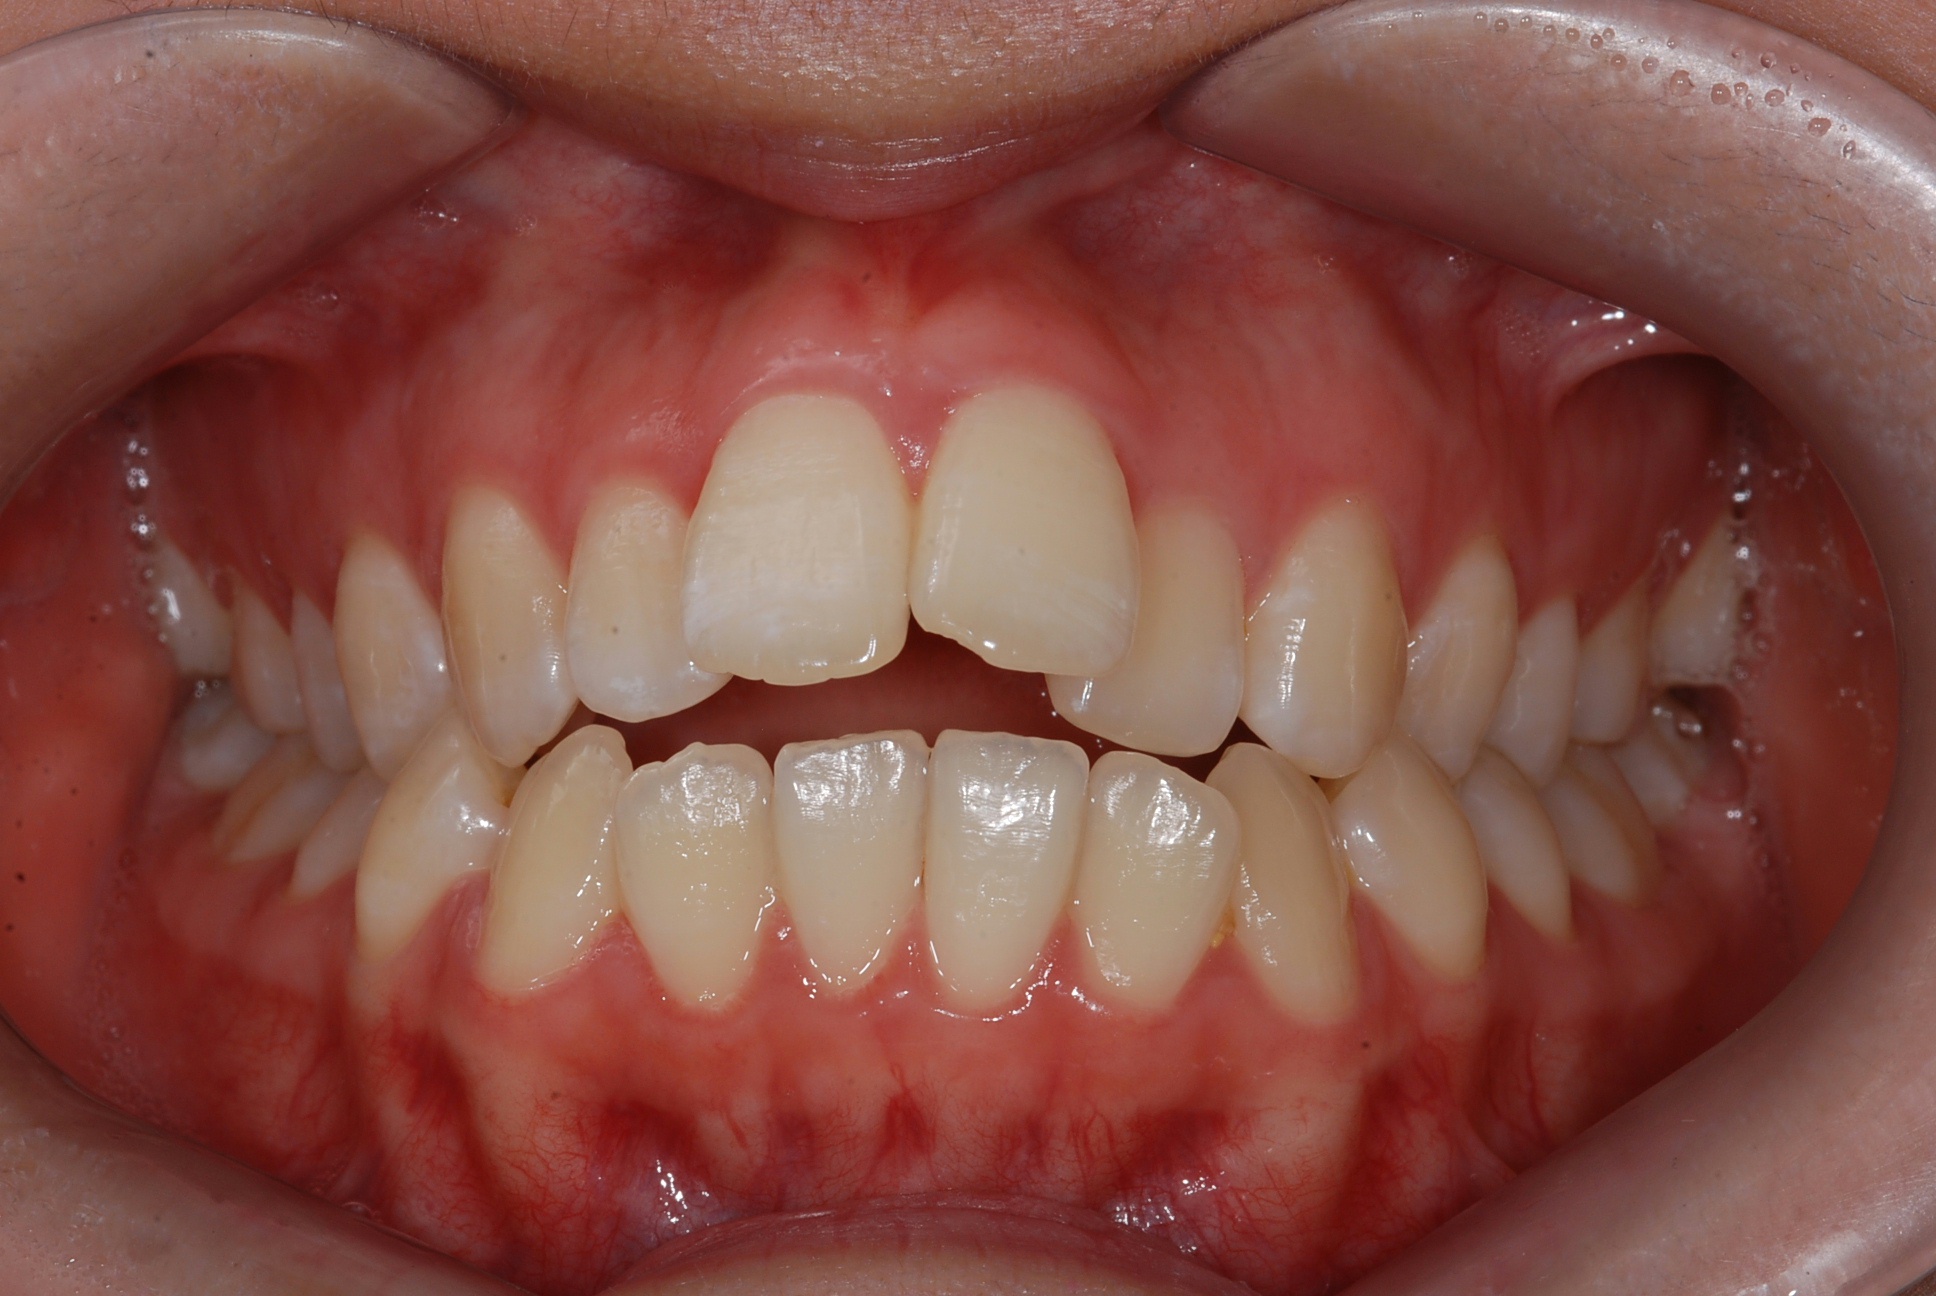

치료 전 사진입니다.